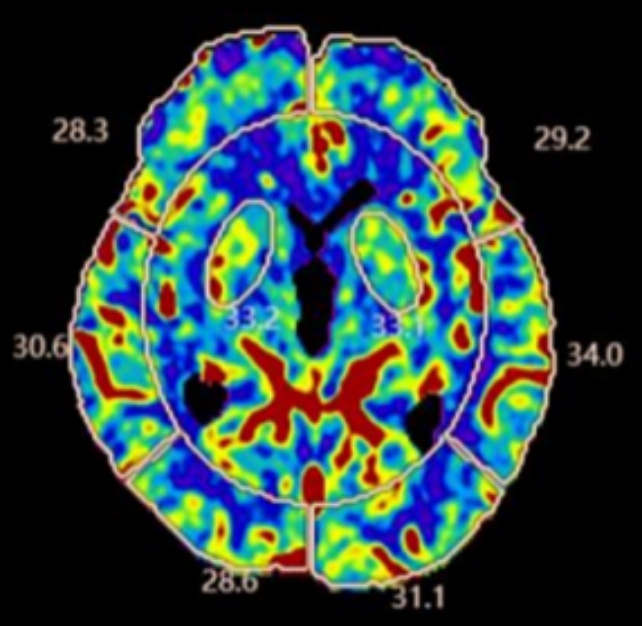

CTP图像于后处理软件(数坤数坤科技股份有限公司)自动勾画椭圆形感兴趣区(ROI),依次选中双侧基底节区、额叶、顶叶、颞叶、枕叶及小脑半球,获得其CBF的测量值平均值。见图1

Figure 1. Shukun cerebral perfusion post-processing software

1. 数坤脑灌注后处理软件